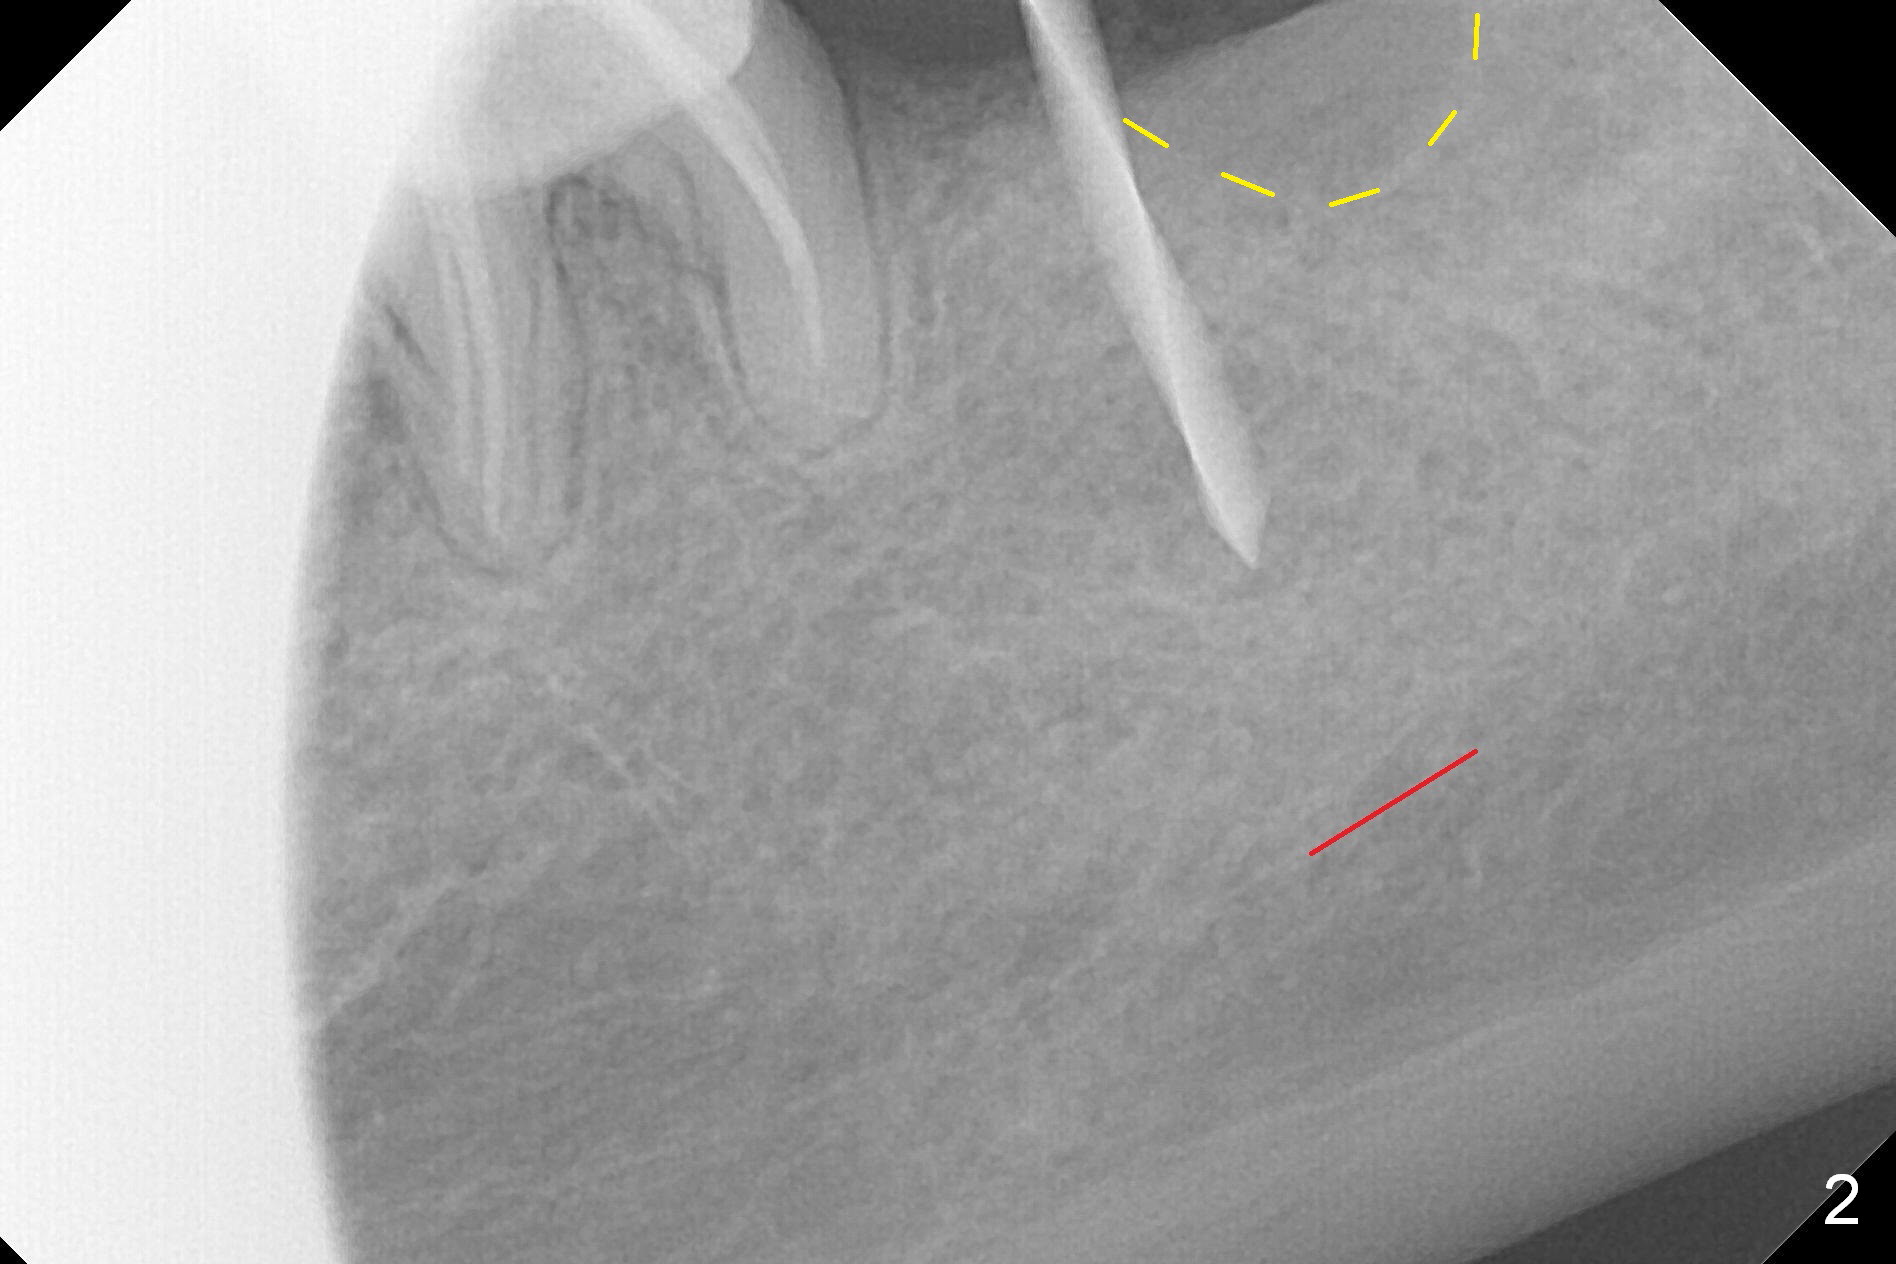

After 1.6 mm pilot drill (Fig.2) and 4.3 mm Magic Drill for 11 mm (gingival margin), a 4.5x11 mm dummy implant is placed with stability (Fig.3). Following Final Drill for 12/13 mm and 4.3 mm MD mesially, a 5x9 mm IBS implant is placed with 40 Ncm (Fig.4). Panoramic X-ray shows the placement is slightly supracrestal (Fig.5). In fact the implant is also placed slightly lingually. When the trajectory is changed, the implant loses stability. When a 5.5x9 mm implant is placed, no stability is achieved (Fig.6). After increase in osteotomy depth for 1-2 mm with MD 4.3 mm, the 5.5x9 mm implant barely obtains stability (~ 10 Ncm, Fig.7). Healing screw is placed. Osteogen plug is inserted in the distal portion of the socket; autogenous bone around the implant and Collagen plug to close the socket opening. Last suture and periodontal dressing are applied.

In fact, the mesial crest of the socket could be used as a more secure landmark (bony vs. soft tissue) for osteotomy depth (Fig.4 arrowhead) with drill stopper. To place the implant subcrestal, the initial osteotomy should be 1-2 mm deeper. When she returns 2 years 9 months postop, the wound has healed. The implant needs to be uncovered. Make sure to have clearance for a healing abutment. Use sensor 1 for PAs before and after uncover. The implant appears to be tilted distal. An angled abutment may be required. Take PA for seating confirmation. Guided surgery is preferable. The implant plateau is covered by the bone 2 years 9 months postop (Fig.8 *). The healing screw is removed with difficulty, while a 6x3 mm healing abutment is placed with resistance, probably related to interference from the distal crest (Fig.9 *). It is much easier with removal of the crest bone using surgical bur, because of clearance (Fig.10 *). It is the best to have a particular drill to remove the excess bone. There is no interference to insert and torque a 5x4(2) mm pair abutment 2 weeks post uncover (Fig.11). Due to poor trajectory (guide necessity) and tight proximal contact, the crown is not completely seated (Fig.12). However, the abutment screw is unlikely to get loose in the future.